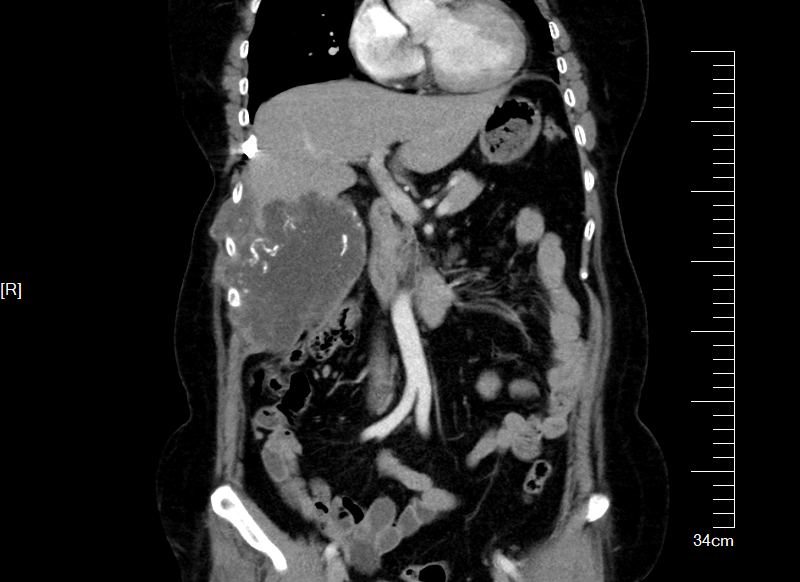

3D模拟肿物与周围脏器关系,正视图与侧视图(黄色为肿物)

通过360度旋转、分层透视,肿瘤与肋骨、肝脏、结肠、右肾以及临近大血管的解剖关系一目了然:肿瘤起源于第7,8肋骨,向胸腹腔内膨胀性生长;肿瘤上界与肝脏S5、S6段分界不清,需要术中探查明确情况,必要时需要切除部分肝脏;结肠及右肾虽毗邻肿瘤边界,但尚未被肿瘤浸润,为功能保留提供可能。

“3D数字医学重建技术不仅可以帮助我们评估手术边界,还提前模拟了术中可能遇到的血管变异和脏器保护难点,让我们能够在完整切肿瘤的同时,尽最大努力保留患者的正常器官组织。”到会的肝胆胰外科古松钢副主任、泌尿外科许哲主任 、胸外科陈少斌副主任、胃肠外科林桂兴主治医师等专家均对3D数字医学重建技术表示认可并讨论制定专科手术协助方案。在充分的讨论后,基于这一“导航图”,MDT团队最终确定了“整块切除受累肋骨及部分肝脏,分离保护结肠及右肾”的手术方案。